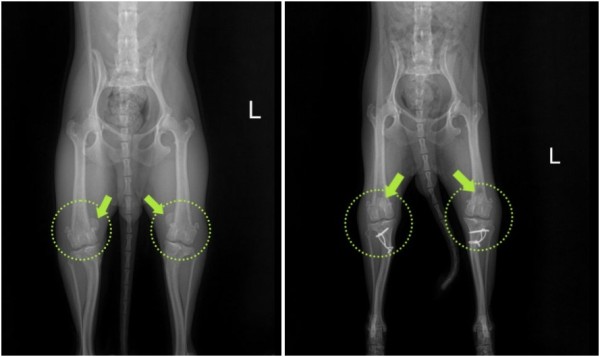

정확한 상태 확인을 위한 검사를 진행한 결과,

양쪽 모두 안쪽으로 슬개골이 빠지는 내측탈구 4기 상태가 확인되었고

통증의 근본 원인을 해결하기 위해 양측 모두 슬개골 탈구 교정술(MPL)을 진행하기로 결정하였습니다.